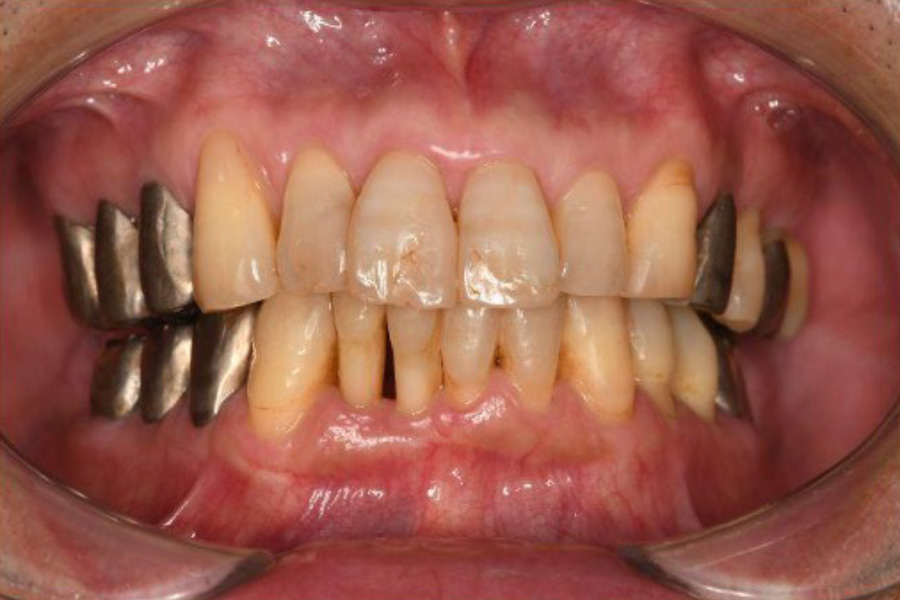

治療後

| 治療内容 | 全顎治療:歯周病治療、抜歯、根管治療、 咬合治療・矯正治療、フルメタルクラウン(保険) |